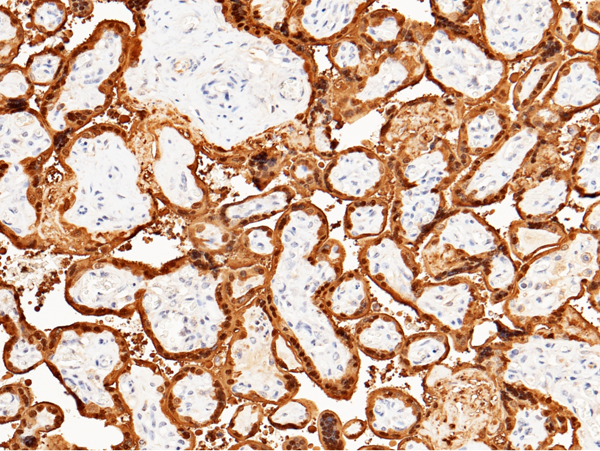

IHC (Immunohiostchemistry)

(Immunochemical staining of human S100P in human placenta with rabbit monoclonal antibody (1:200, formalin-fixed paraffin embedded sections). The image showing nucleus staining of trophoblastic cells.)